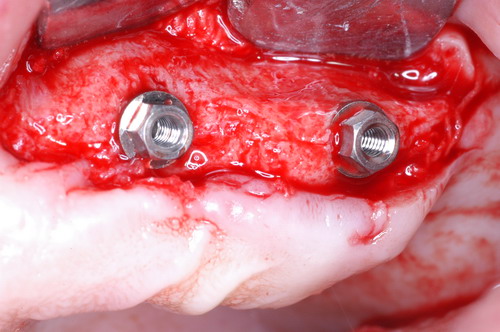

EL USO DEL ARCO GÓTICO DE GYSI , MEDIANTE UNA BÓVEDA PALATINA Y UN APOYO CENTRAL ÚNICO (BO PA YA CU) , EN LA UBICACIÓN DE LA RELACIÓN CÉNTRICA EN UN CASO DE GRAN LAXITUD TENDINOSA CAPSULAR. EL PACIENTE SE PRESENTA A CONSULTA CON UNA EDENTACIÓN PARCIAL, Y GRADO DE MOVILIDAD EXTREMO EN TODAS SUS PIEZAS REMANENTES. SE ESTUDIA EL CASO RADIOGRÁFICA Y CLÍNICAMENTE , Y EL PACIENTE RELATA ESTAR EN ESE ESTADO DESDE HACE MUCHO AÑOS. AL MANIPULAR LA MANDÍBULA EN UN INTENTO DE CONOCER EL ESTADO MUSCULAR DEL SISTEMA, SE OBSERVA UNA GRAN LABILIDAD TENDINOSA CAPSULAR QUE SE MANIFIESTA EN UNA HIPER LAXITUD EN LOS MOVIMIENTOS MANUALMENTE INDUCIDOS DE AMBOS CÓNDILOS DENTRO DE LA CAVIDAD. SE TOMAN IMPRESIONES Y SE MONTA EN UN ARTICULADOR SEMI AJUSTABLE , CORTANDO EN EL YESO LAS PIEZAS QUE SERÁN EXTIRPADAS , CONSERVANDO UNICAMENTE , AMBOS PRIMEROS PREMOLARES INFERIORES , QUE SERÁN UTILIZADOS PARA RETENER MEDIANTE RETENEDORES ELÁSTICOS LA PRÓTESIS INFERIOR , EN LA PRESUNCIÓN DE LA HIPERMOVILIDAD A QUE SERÁ SOMETIDA DADO QUE EN LA GRAN REABSORCIÓN ÓSEA , ES FRECUENTE EL ACERCAMIENTO DE TODAS LAS INSERCIONES MUSCULARES A LA PORCIÓN SUPERIOR DEL REBORDE ÓSEO , LO QUE ATENTARÁ CONTRA LA ESTABILIDAD DE DICHA PRÓTESIS PROVISIONAL. EN UNA PRIMERA SESIÓN CLÍNICO QUIRÚRGICA , SE EXODONCIA TODO EL SECTOR INCISIVO Y CANINO INFERIOR , Y AL OBSERVAR EL REMANENTE ÓSEO CANINO DE AMBOS LADOS , SE IMPLANTA EN FORMA INMEDIATA . TANSCURRIDOS DOS MESES , DONDE LA CICATRIZACIÓN ES ADECUADA , Y LA DINÁMICA MANDIBULAR ACEPTABLE , SE PROCEDE A LA ETAPA QUIRÚRGICA IMPLANTARIA MEDIANTE IMPLANTES SEMI SUMERGIDOS, CON ALGUNAS ZONAS DE REGENERCIÓN ÓSEA GUIADA FIG17 FIG18 FIG19 FIG26 DURANTE LA ETAPA DE CICATRIZACIÓN DE ESTE NUEVO ABORDAJE QUIRÚRGICO , SE ENDODONCIAN AMBOS PREMOLARES INFERIORES CONSERVADOS , LOS QUE EN UN FUTURO , CUANDO YA NO SIRVAN PARA RETENER LA PRÓTESIS REMOVIBLE PROVISORIA INFERIOR , SERÁN CORTADOS COMO RESERVA DE CAPITAL ÓSEO O BIEN COMO ELEMENTO RETENEDOR ANTE CUALQUIER TIPO DE INCIDENCIA IMPLANTARIA. ABORDAMOS LA ETAPA PRIMARIA PROTÉTICA , UNA VEZ TRANSCURRIDOS TRES MESES, MEDIANTE LA UTILIZACIÓN DE CUBETAS INDIVIDUALES , A LAS QUE REALIZAMOS UN RECORTE MUSCULAR EN BASE A STENS VERDE , COMO SI DE UNA PRÓTESIS COMPLETA SE TRATARA. DE ESE MONTAJE OBTENEMOS DOS RODETES DE METACRILATO , PERFECTAMENTE ADAPTADOS A LOS MODELOS FUNCIONALES , A LOS QUE LES OTORGAMOS LA PLANIMETRÍA DERIVADA DEL PARALELISMO CON EL PLANO DE FRANKFURT , Y UNA ALTURA (DV) QUE RESULTA DE LOS MÉTODOS MÉTRICOS DE DIMENSIÓN VERTICAL… Y QUE NOS SERVIRAN ADEMÁS DE TOMAR UNA NUEVA IMPRESIÓN FUNCIONAL MEDIANTE RECORTE MUSCULAR , PARA ADAPTAR UN DISPOSITIVO CONSISENTE EN UNA BÓVEDA PALATINA SUPERIOR , Y UN TORNILLO CENTRAL INFERIOR , LOS QUE DESPUÉS DE UN ENTRENAMIENTO ADECUADO DEL ENFERMO , NOS PERMITIRÁ REPRODUCIR EN EL BÓVEDA , EL ARCO GÓTICO DE GYSI , ENCONTRANDO DE ESTA MANERA LA OCLUSIÓN EN RELACIÓN CÉNTRICA. ACTUALMENTE ESTE MÉTODO HA SIDO RECREADO MEDIANTE LA DENOMINACIÓN DE: FIG50 FIG51 FIG52 OBTENIDO EL DIBUJO DEL ARCO GÓTICO , INSINUAMOS EN EL VÉRTICE DEL MISMO UNA PERFORACIÓN QUE FIJARÁ LA PUNTA DEL TORNILLO EN ESA POSICIÓN: RELACIÓN CÉNTICA FIG55 FIG56 FIG57 CON ESTOS PARÁMETROS SE CONSTRUYEN DOS SOBREDENTADURAS ABROCHADAS EN RÓTULAS SUPRA IMPLANTES , QUE LE OTORGAN FIJACIÓN SUFICIENTE , DANDO A LA OCLUSIÓN TODOS LOS ELEMENTOS DE UNA: OCLUSIÓN MUTUAMENTE COMPARTIDA, REFERENCIA II CON UN ESQUEMA OCLUSAL DE : FUNCIÓN DE GRUPO BILATERAL POSTERIOR DE ACCIÓN CANINA DESPUÉS DE LAS REVISIONES PERTINENTES A LA SEMANA , EL MES Y LOS SEIS MESES DE TERMINADA LA REHABILITACIÓN , SE CITA AL ENFERMO PARA UN NUEVO CONTROL AL AÑO Y MEDIO Y SE OBSERVA UNA PERFECTA SITUACIÓN TISULAR , CLINICA Y RADIOGRAFICAMENTE CONTROLADA , Y ADEMÁS LA PERMANENCIA DEL MISMO ESQUEMA OCLUSAL OTORGADO DESDE EL PRINCIPIO. SE CONTROLA RADIOGRAFICAMENTE Y SE DA EL ALTA DEFINITIVA RECOMENDANDO EL CONTROL DOS VECES AL AÑO. REFERENCIAS: I : II. : III: